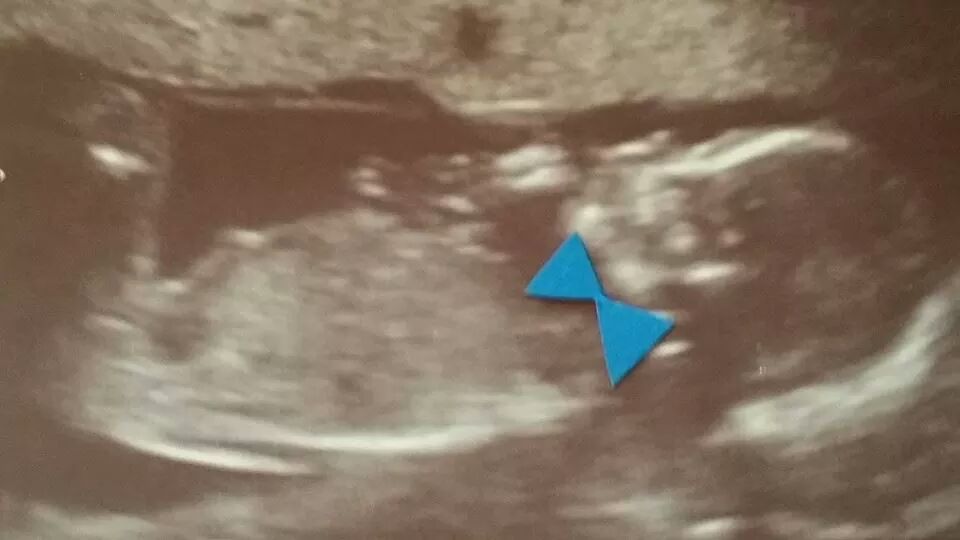

Baby Boy #4 for us! Can't believe it!

I got some not so great news though. I'm now considered high risk due to a velamentous cord. Basically a section of the cord is exposed and not protected. I go in monthly for ultrasounds to check on the growth of the baby and starting around 30 weeks I'll go in for weekly monitoring. Dr. Said it's more then likely I won't go to full term, but shooting for the best here and staying optimistic.